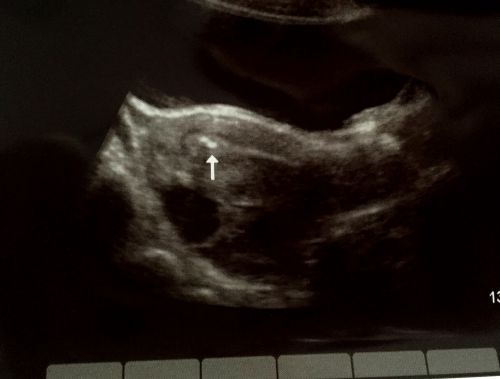

矢印は体内の受精卵を示しています。11月17日撮影

先に、結果をご報告。パリ在住の友人は、バルセロナに4日間のみ滞在し、手術を受け妊娠に成功いたしました。